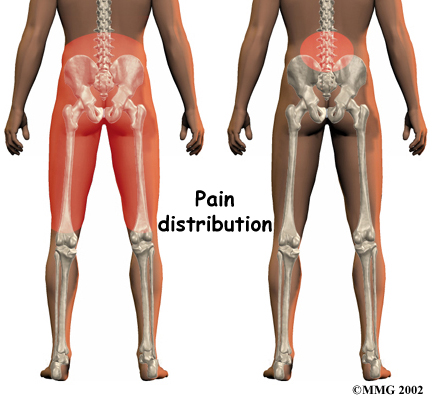

Pain in the center of the low back is often the first symptom patients feel. It usually starts to affect patients in their twenties and thirties. Pain tends to worsen after heavy physical activity or staying in one posture for a long time. The back may also begin to feel stiff. Resting the back eases pain. At first, symptoms only last a few days.

This type of back pain often comes and goes over the years. Doctors call this recurring back pain. Each time it strikes, the pain may seem worse than the time before. Eventually the pain may spread into the buttocks or thighs, and it may take longer for the pain to subside.